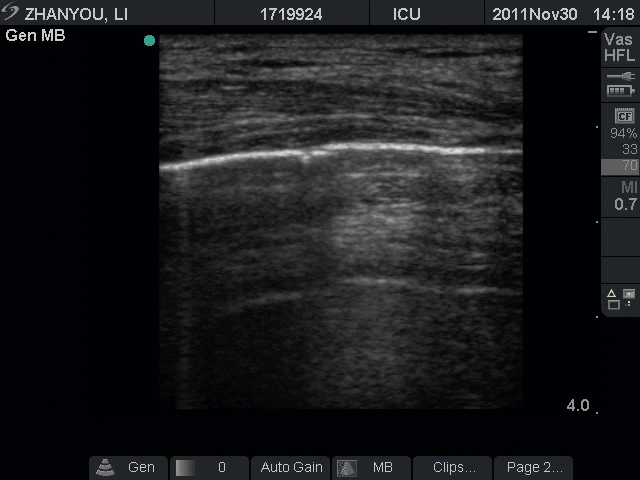

跬步千里frommon重症超声规范化诊治流程8气胸诊治流程

张力性气胸要先脱气再插入胸腔导管.